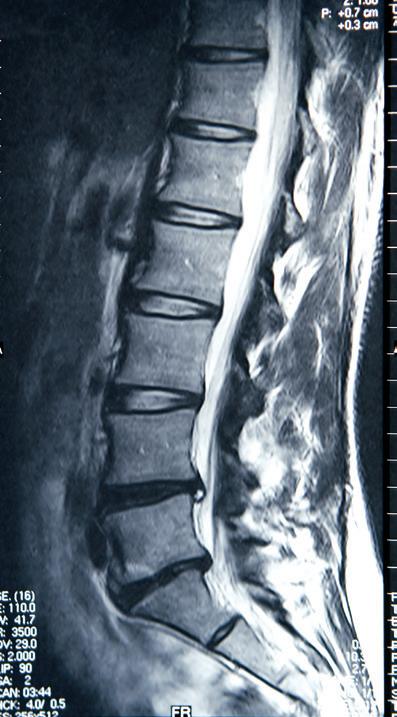

MRI

Magnetic resonance imaging (MRI) is a non-invasive study that uses magnetic energy and radio waves, not radiation, to produce a detailed two- or three-dimensional image of structures inside the body. MRI scans map the location of water and fat in the body and produce detailed spatial images. MRI is a useful tool for diagnosing and monitoring myeloma because of its ability to image early focal lesions in the bone marrow. Because MRI creates images of soft tissue, it can show small clumps of myeloma in the bone marrow, plasmacytomas, and compression of the spinal cord by these masses.

The best setting for MRI is early in diagnosis. MRI is highly sensitive for the detection of focal lesions before bone destruction occurs. In a large comparative study of X-ray and MRI, 52% of patients had normal-appearing

whole-body X-ray but had focal lesions that were apparent on MRI. The IMWG guidelines on MRI state that because MRI is a more sensitive study than X-ray for focal lesions (before the appearance of lytic bone lesions), all SMM patients should undergo whole-body MRI (WBMRI) or spine and pelvic MRI if WBMRI is unavailable.

The limitations of MRI include the following:

¡ MRI is an expensive, timeconsuming procedure.

¡ Patients who have metal implants, and patients who are claustrophobic, cannot undergo MRI.

13. Example of an MRI study

¡ There is a lag time of about 9 months or longer before an MRI will look normal after an area of myeloma has been successfully treated. Because this leads to a high falsepositive rate, the IMWG guidelines state that the use of MRI “for the follow-up of patients, before or after different therapies, in the absence of clinical indications is not recommended.”

¡ Treatment for myeloma will interfere with MRI results. If possible, myeloma patients should not start treatment before a scheduled MRI.

¡ The MRI scanning technique that is best for myeloma (with diffusionweighted imaging) has not been standardized and is not widely available.